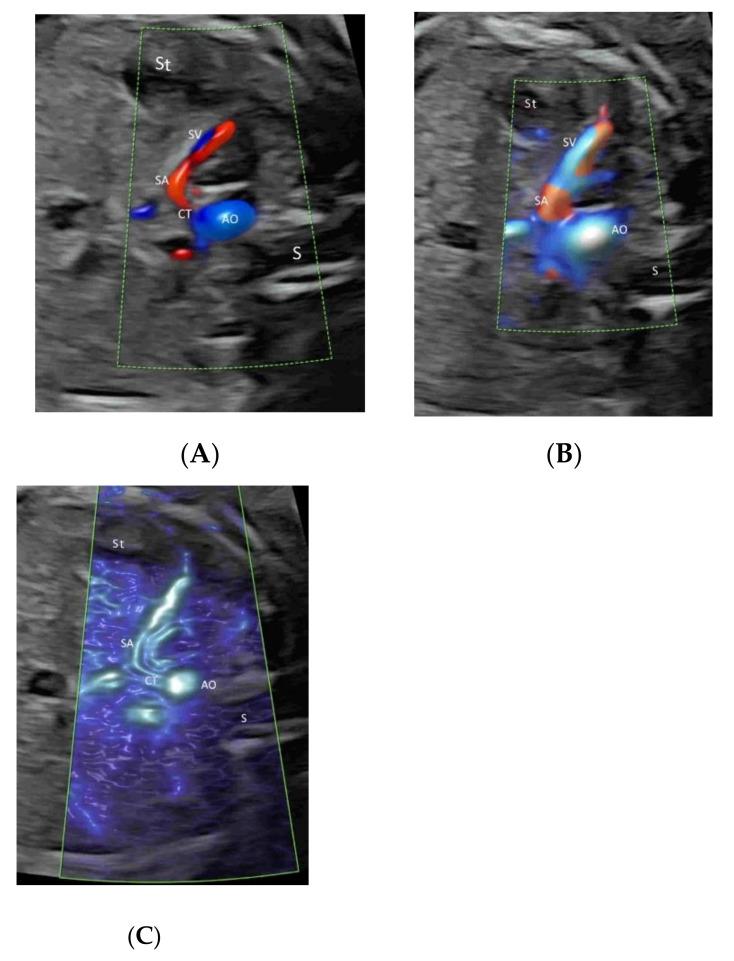

Color flow imaging (CFI), being non-invasive, is commonly used in obstetrics to study the fetal and placental circulations. The conventional CFI modes include color Doppler flow imaging (CDFI) and power Doppler imaging (PDI). In recent years, there is increasing use of new modes, including high-definition flow imaging (HDFI), radiant flow, microvascular flow imaging (MVFI), and three-/four-dimensional rendering in glass-body mode. Compared to CDFI, HDFI can show a higher resolution and sensitivity and allow the detection of slower flows. MVFI increases the sensitivity to fine or low-flow vessels while producing little or no motion artifacts. Radiant flow shows the blood flow with a sense of depth and reduces blood overflow. Glass-body mode, showing both gray-scale and color-flow information, can demonstrate the heart-cycle-related flow events and the vessel spatial relationship. In this review, the characteristics and applications of the various CFI modes in obstetrics are discussed. In particular, how these new technologies are integrated in detailed diagnostic and early morphology scans is presented.